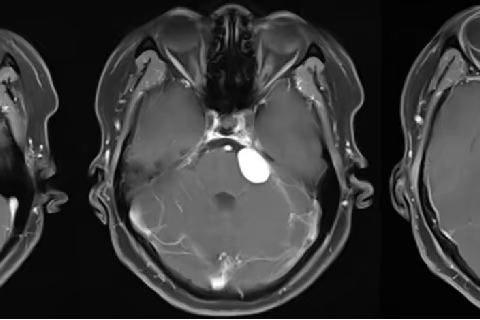

神经外科三病区成功开展我市首例3DSlicer术前规划、术中电生理监测切除岩尖脑膜瘤